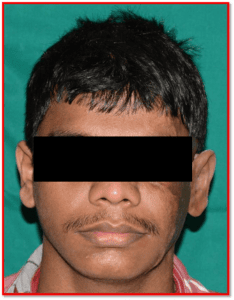

The Department of Prosthodontics and Crown & Bridge, in association with various Departments of Goa Medical College (Neurosurgery, Plastic Surgery, Surgery, Ophthalmology, and ENT), carries out complex rehabilitations of patients suffering from various developmental and acquired defects.

- Prostheses for maxillofacial defects